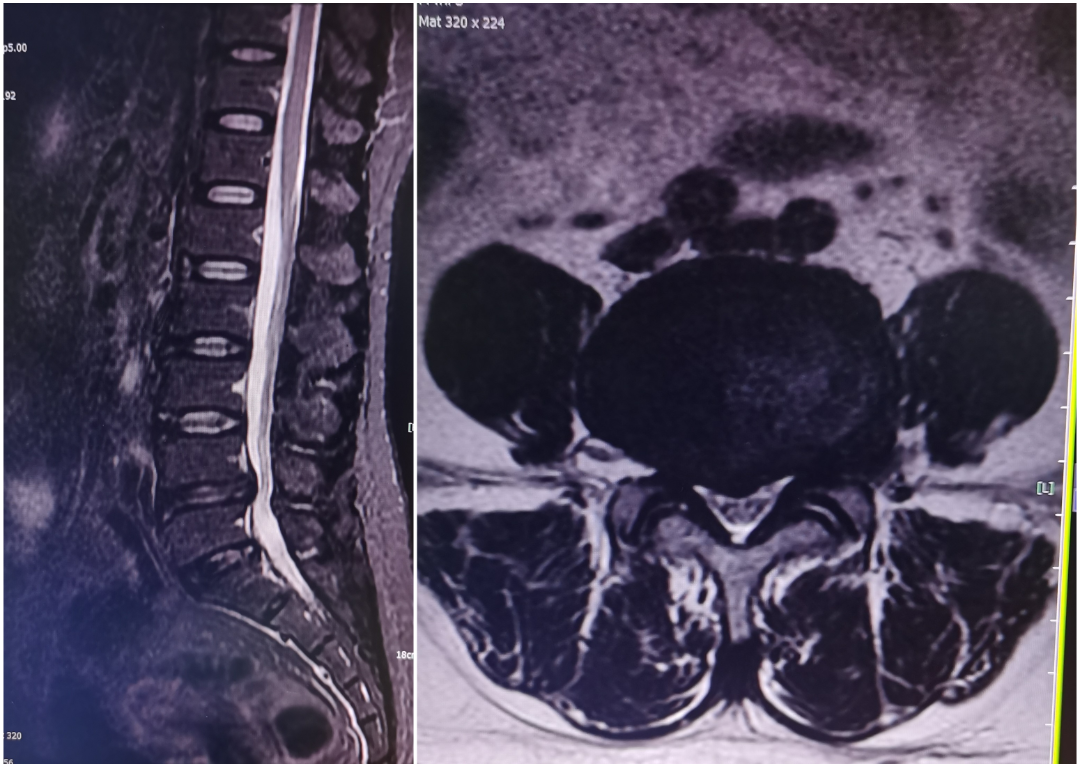

UBE镜下融合经皮固定(Ulif)

黄某,71岁男性患者,因反复腰部疼痛3年余,再发加重1周入院,查体:脊柱生理弯曲存在,腰部无明显肿胀,未扪及明显台阶感,下腰段椎间隙压痛,椎旁肌稍压痛及叩击痛,双下肢萎缩,右侧直腿抬高试验及加强试验阳性,右足第1趾背伸及跖屈伸肌力减弱,右大腿外侧、小腿外侧、后侧及足背外侧感觉麻木,左下肢感觉正常,结合辅助检查,诊断:腰椎管狭窄症:腰4/5椎间盘突出,于全麻下行经单侧双通道脊柱内镜下腰4/5椎板开窗减压、腰4/5椎间盘摘除、椎间cage植骨融合、经皮钉棒系统内固定术。患者术后腰部及双下肢麻痛症状明显改善。

术前影像学

术中透视、术后复查